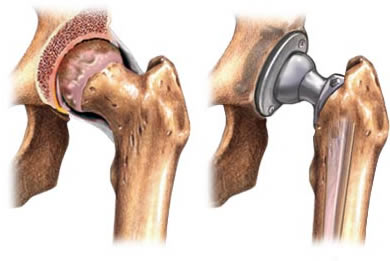

هل ترغب في التخلص من آلامك وأوجاعك نهائياً وتود معرفة سعر مفصل الفخذ السيراميكي ؟ آلام المفاصل واحدة من أكثر الآلام وجعاً والتي لا تذهب حتى من المسكنات، ويرجع السبب إلى تلف كامل وتآكل في تلك المنطقة لا يُجدي علاجها ولا يزول الألم، وتصعب معه ممارسة الأنشطة اليومية ومنها المشي، ليكون خيار إجراء الجراحة هو القرار الوحيد للتخلص من كل تلك الآلام. ولأن لكل مشكلة حل، ف الأطراف الصناعية واحدة من أبرز وأفضل الحلول في وقتنا الحالي التي أصبحت بديل آمن والحل الأفضل لتلك المشكلة التي يعاني منها كثير من الناس.

وتحدث تلك المشكلة نتيجة العديد من الأسباب منها التعرض إلى الحوادث، والتقدم في السن، وضعف المناعة والإصابة بالسمنة والمضاعفات التي تحدث نتيجتها من ضغط شديد على تلك المنطقة، وغيرها الكثير من الأسباب التي تسبب مشاكل كبيرة للجسم وخاصة الجزء السفلى، ومنها حدوث التهابات شديدة بمنطقة الورك التي تؤدي إلى الآلام شديدة بمنطقة الورك ويتطلب علاج تلك الحالة إجراء عمليات تغير المفصل واستبدال بآخر صناعي، وهى من الجراحات البسيطة والآمنة تماما، ويستطيع المريض بعدها أن يعيش حياته بشكل طبيعي، حيث يمكنه المشي والحركة بصورة طبيعية.

توجد العديد من أنواع المفاصل الصناعية المستخدمة في تلك العملية، والتي تتفاوت في جودتها من الرديء إلى المتوسط والأفضل.

وبشكل عام فإن المفاصل الصناعية للفخذ تتكون من ثلاثة أجزاء: السبيكة المعدنية والسطح الناعم والمادة التي تربط المفصل وسبائكه بعظام الإنسان.

أما بالنسبة لطريقة تثبيت المفصل في العظام، فهناك أنواع عديدة منها أسمنت العظام، وهو مادة تربط المفصل بتجاويف العظام، ومنها مادة الهيدروكسى أباتيت وهى مادة يتفاعل معها العظام وتلتئم معها مثل التئام الكسور، ومنها أسطح أخرى للمفاصل تسمح بنمو خلايا العظام بداخلها والتصاق العظام بالمفصل.

توجد أشكالا كثيرة ومتنوعة للمفاصل بحيث تناسب حالة المريض فمنها أنواع مستقيمة وأنواع أخرى منحنية وأنواع قصيرة للدخول في تجويف عظمة الفخذ، ومن ناحية أخرى هناك أيضا أشكال وأنواع كثيرة لمفصل الحوض، حيث تناسب شكل مفصل المريض وتناسب حالته.

عملية اختيار نوع المفصل من أهم الخطوات التي يجب إتباعها والتي يتوقف عليها نجاح العملية أو فشلها، حيث يقوم الطبيب بتحضير أنواع مختلفة من المفاصل حتى تناسب حالة المريض لتحقق الوظيفة المطلوبة بدرجة نجاح عالية، كما أن هناك تفاصيل أخرى كثيرة يجب مراعاتها في التخطيط للجراحة وتنفيذها لضمان نجاح العملية، وأغلب المفاصل الصناعية يتم السماح للمريض فيها بالمشي من اليوم الأول بعد الجراحة بشرط توفر العوامل المناسبة لاستقرار المفصل والتئام الأنسجة العضلية المحيط.

تبدأ العملية من خلال قيام الجراح بعمل شقوق فوق الجزء الأمامي أو الجانبي من الورك من خلال طبقات الأنسجة، بعدها يتم إزالة العظام المريضة أو التالفة وكذلك الغضاريف مع ترك العظام السليمة دون المساس بها، ثم يقوم الطبيب بزراعة تجويف للأطراف الصناعية في عظام الحوض، لاستبدال التجويف التالف، وفي النهاية يتم استبدال الكرة المستديرة أعلى الفخذ بكرة صناعية والتي يجري تركيبها في الجذع المناسب في عظمة الفخذ.

يتم تعريف تلك العملية بأنها عملية جراحية يتم من خلالها استبدال مفصل الورك كاملاً بمفصل صناعي من المعدن أو البلاستيك، وتتم تلك العملية تحت تأثير التخدير النصفي لمنطقة الجراحة أو بالتخدير العام للجسم كله، إذ يكون المصاب عندها غائبًا عن الوعي، وتهدف إلى استبدال العظمتين التالفتين لخلق مُسطّحين جديدين في المفصل ليعمل المفصل أفضل، ويقوم الطبيب بتحديد طريقة التخدير المستخدمة بناءً على وضع المصاب، وحالته الصحية.